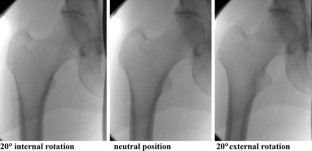

With the help of a C-arm image intensifier, five surgeons tried to determine the neutral state of ten prepared cadaver femora. They could only look at the C-arm screen and were blinded to the actual femur. Per observer three measurements were done per femur. The first measurement (method I) was done without a reference, while the second (method II) used a reference image of the femur in a neutral state. The third method (method III) added a lesser trochanter quantifying computer program. After positioning of the femur, the difference in rotational state compared with the neutral state was measured with an inclinometer.

Fig. 1